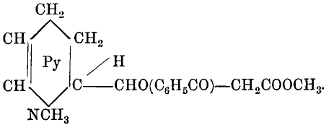

| Brucine Hydriodide, | 342 | |